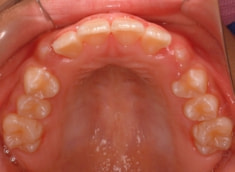

治療前

治療開始時

上顎の劣成長が顕著なので、上顎犬歯の萌出するスペースが不足しています。

また、統計通り、左上の犬歯です。